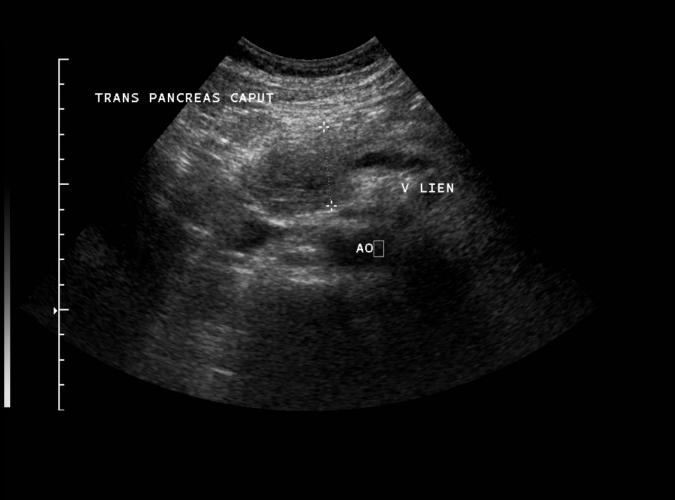

(a) Trans. 48årig patient med lågekogen tumör centralt i caput pancreas ..se 6b long bild.